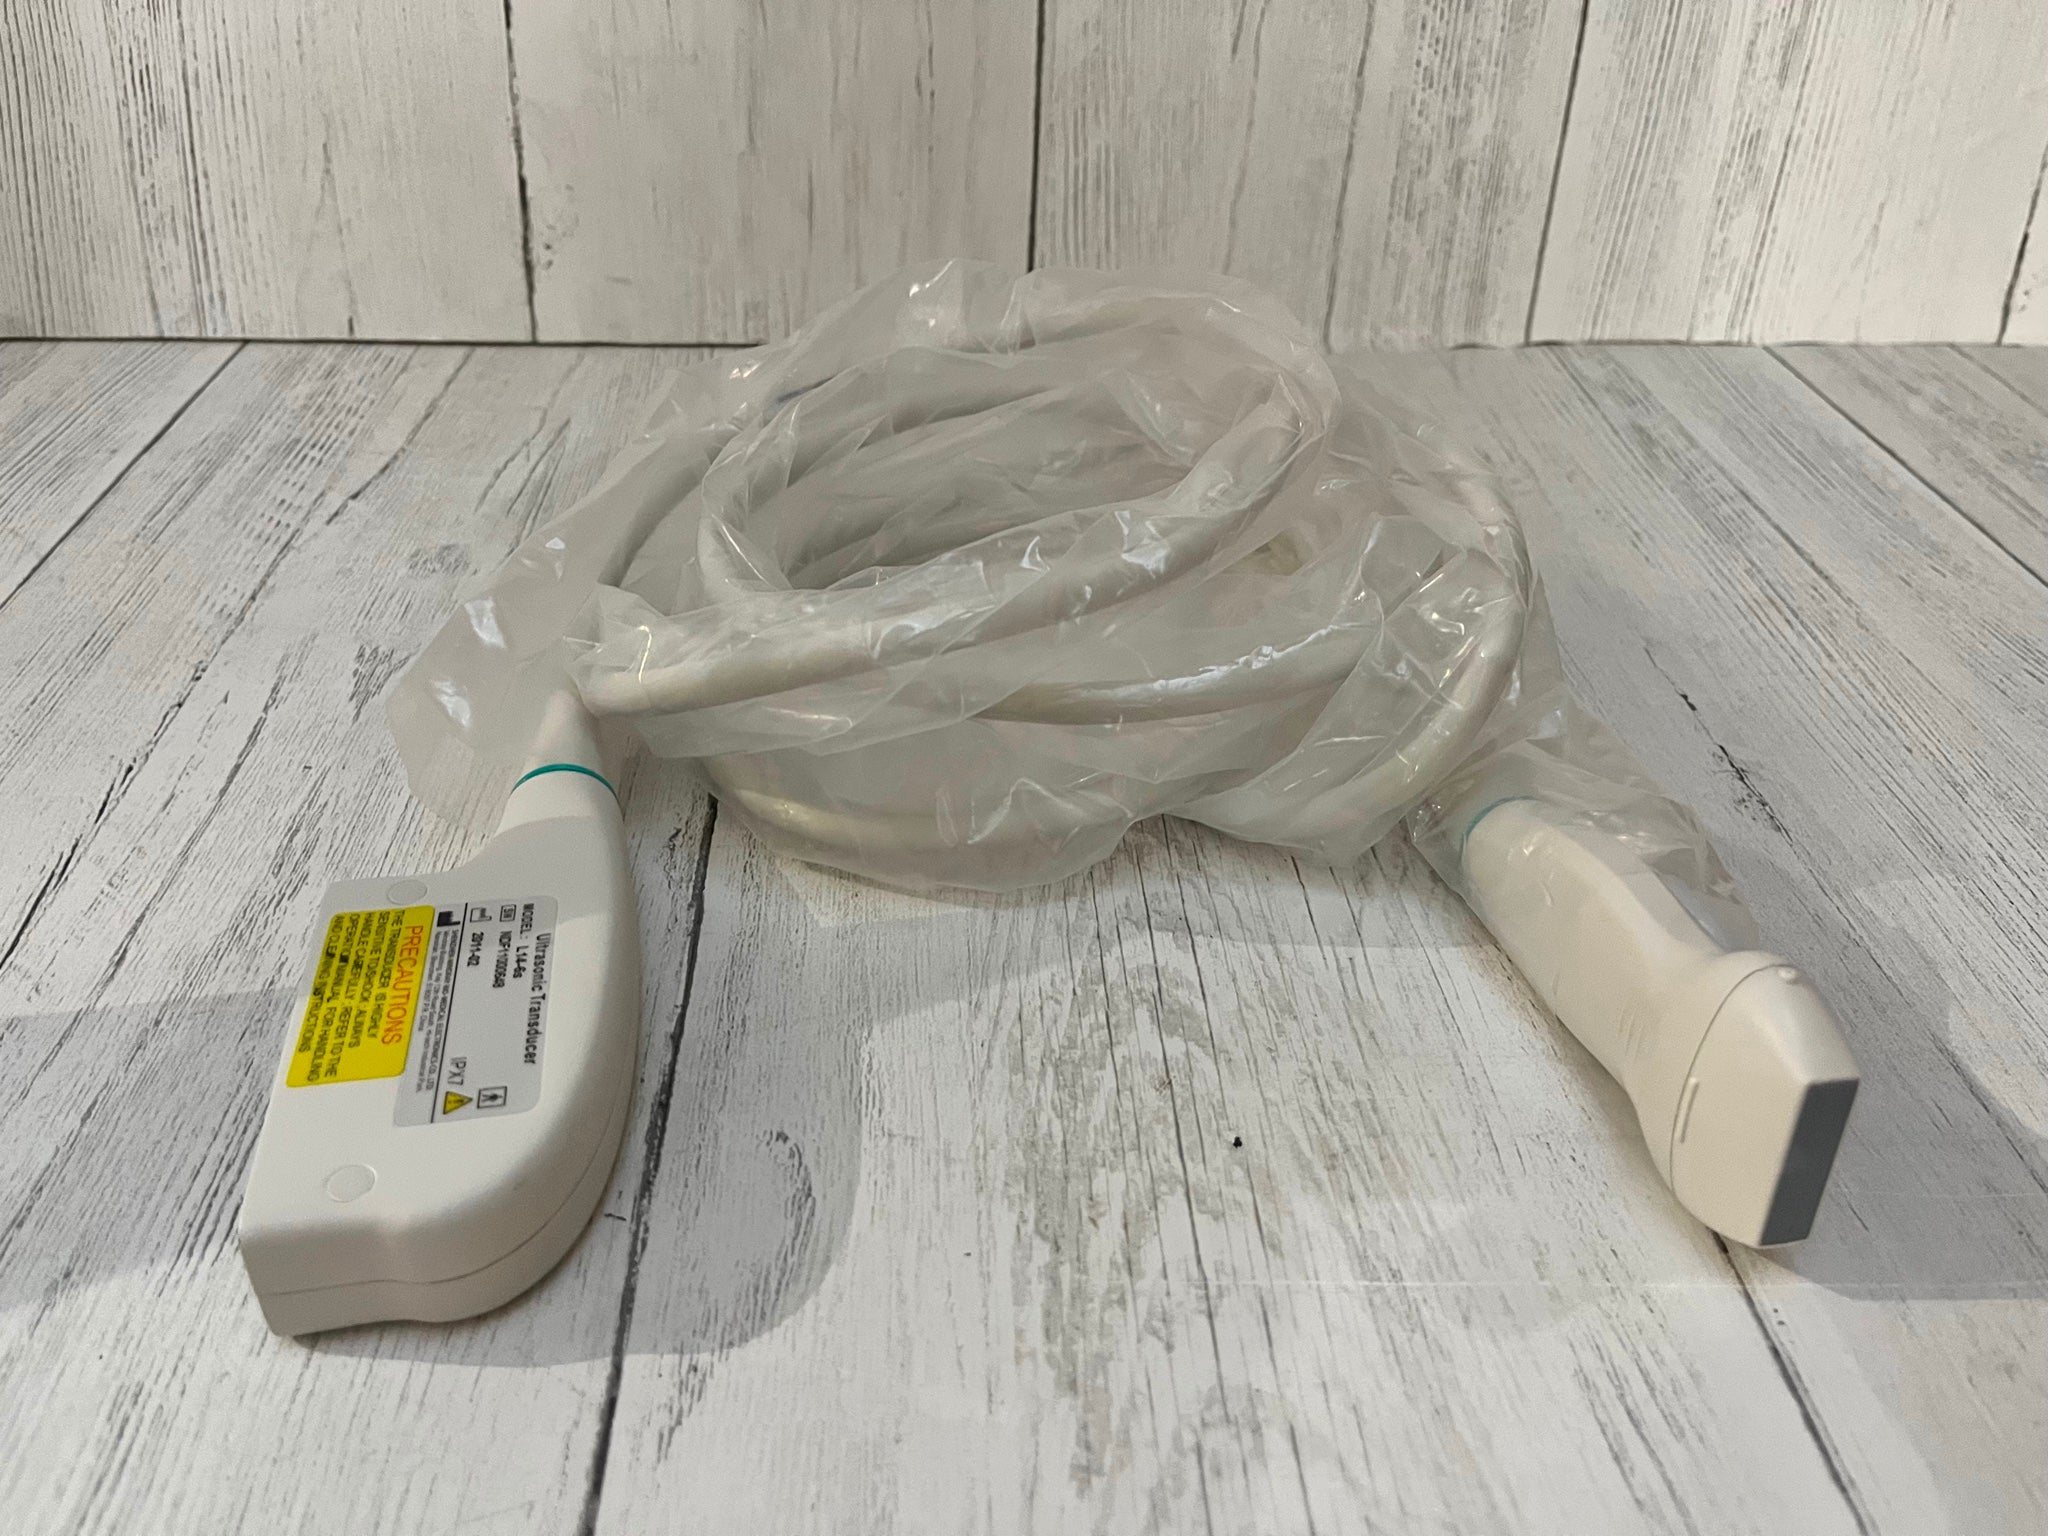

The laptop ultrasound scanner

utilizes state-of-the-art technology to provide clear and accurate imaging, essential for diagnosing various medical conditions. With both transvaginal and convex probes, it caters to a wide range of examinations. This versatility ensures healthcare professionals can perform different types of scans with a single device, making it incredibly efficient. Moreover, the scanner’s lightweight design allows for easy transport, which is particularly beneficial in emergency medical situations.